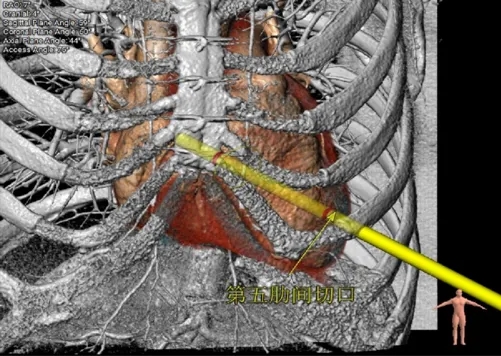

瓣环切线位:右30度,头43度

第五肋间切口

工作角度-瓣环切线位:RAO39°CRA38°

瓣环切线位:RAO60°,CRA20°

第五肋间切口,心尖轻度转位,过肋弓,靠近胸骨中线方向

投照角度:RAO42°,CRA49°

肋间选择